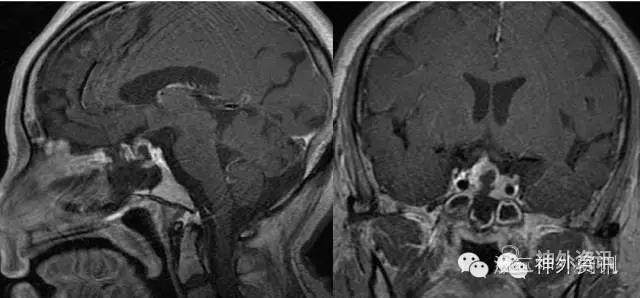

垂体转移瘤比较少见,文献报道约占垂体肿瘤的1%[1]。统计我科2012年3月至2016年5月的资料,共245例转移瘤,只有1例(0.41%)经病理证实为垂体转移癌。患者为女性,65岁,以“头痛1月”入院,垂体MRI发现垂体占位病变(图8A-D),行经蝶显微肿瘤切除术。术前肿瘤标记物正常,术中冰冻及术后常规病理均提示为转移性腺癌,考虑乳腺癌或肺癌转移可能,但PET-CT及乳腺、胸部的相关检查均阴性。术后MRI显示肿瘤全切(图8E),鉴于为转移性肿瘤,术后予局部放疗,44个月随访时一般情况良好,复查垂体MRI示局部囊变,未见复发(图8F)。

图8. 术前MRIT1平扫,T2及T1强化片(A-D),显示垂体肿瘤,强化不明显;术后复查显示肿瘤全切(E);术后44个月(放疗后)复查未见复发(F)。